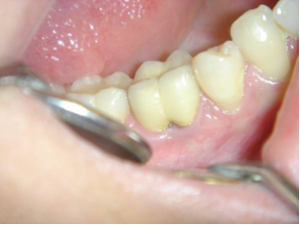

Perforation du placher pulpaire et faux canal.

Perforation du plancher pulpaire et faux canal.